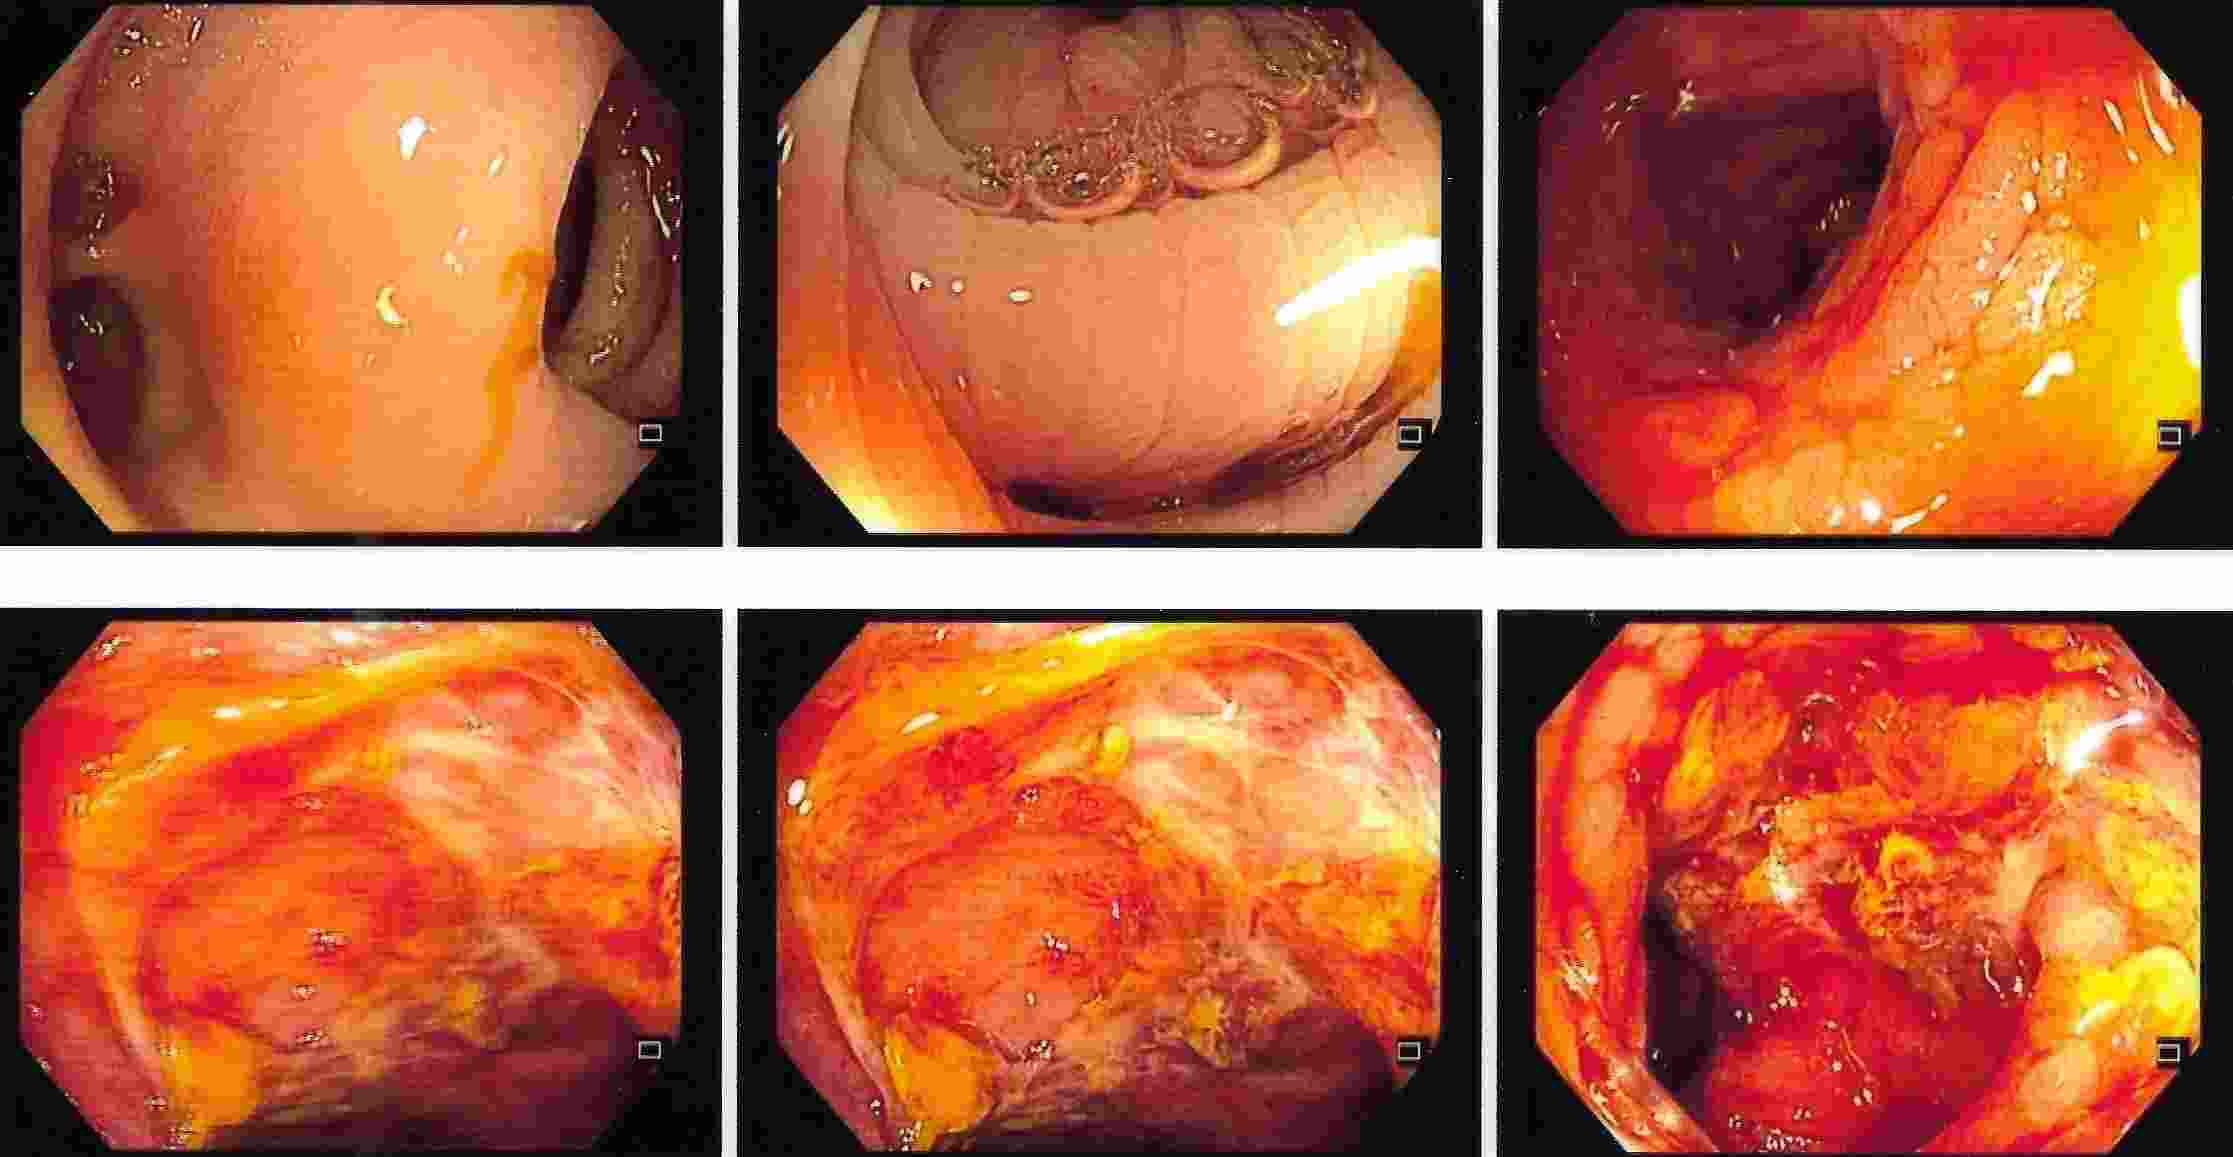

COLONOSCOPY

Colonoscopy is a procedure where the doctor can examine the lowermost part of the digestive tract

by a flexible instrument called as Colonoscope. Common indications for Colonoscopy are

7. Frank blood in the stool, occult blood in the stool or anaemia.

These conditions are seen more often in elderly people where Colonoscopy is essential for making an early diagnosis of cancer of the colon.

Common mistake is to attribute blood in the stool for piles or fissure and get wrongly treated for a long time.

The correct diagnosis of cancer of the colon or rectum if made in time can offer a curative treatment.

Major bleeding in the stool in elderly people is commonly due to diverticulitis of colon.

This is a condition where there are balloon like projections arising from colonic mucosa and

which bleed due to rupture of a blood vessel. Colonic polyps is also an important condition to diagnose because

polyps have potential of becoming cancerous in future. Removal of polyp by polypectomy without

open surgery can offer cure in the early stage of cancer. A proper follow-up can keep the patient free from cancer.

Cancer of the Colon